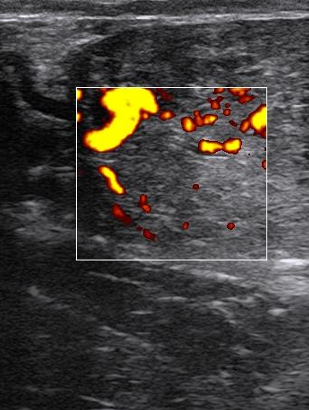

How can ultrasound be used to determine bloodflow?

doppler —> frequency of reflected wave changed by movement of structure as reflects the wave

will show higer frequency if blood moving towards scanner

What can you identify on ultrasound relating to cardiology?

• Valve incompetence

• Ventricular septal defects, PDA

• Doppler – see direction of flow as colour

• See valve motion and cardiac cycle – correlate with murmur